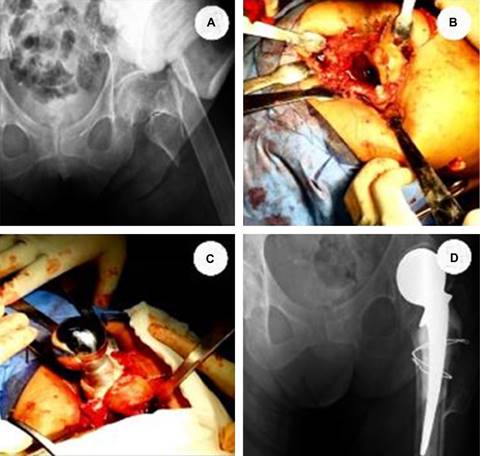

Las FC transtrocantéricas en los pacientes adultos mayores se asocian a una alta mortalidad, siendo de 7.1% a los 30 días y de 28.1% al año, por lo que intervenir quirúrgicamente ha demostrado beneficios por ser segura, paliativa y rentable.17,18 Dentro de estas intervenciones está la colocación de la hemiprótesis de Thompson (HT), siendo rápida, simple y paliativa para la movilización temprana. La pertinencia de realizar este estudio recae en conocer y tener la mejor evidencia de cuál es la recuperación funcional tras la colocación de HT en un hospital público de la Ciudad de México (Figura 1).

Se realizó un estudio prospectivo, observacional, longitudinal y unicéntrico, donde se reclutaron a pacientes mayores de 80 años de edad o más que fueron atendidos en el Hospital Regional “Gral. Ignacio Zaragoza” del Instituto de Seguridad y Servicios Sociales de los Trabajadores del Estado (ISSSTE) en el periodo de enero de 2019 a diciembre de 2020. Tras previa explicación y firma de consentimiento informado por parte del paciente o un familiar legalmente responsable, y bajo la normatividad del Comité de Ética local, se incluyó a pacientes diagnosticados con FC transtrocantérica clasificaciones Tronzo IIIB-V, a los cuales se les realizó sustitución del calcar mediante el uso de injerto óseo autólogo con cerclaje a trocánter menor para conseguir el apoyo necesario para la colocación de una hemiprótesis de Thompson. Posteriormente, los pacientes fueron evaluados clínicamente en consulta externa, con base en la escala HHS (Tabla 1), siendo aplicada a los 15 días, un mes y tres meses. Se excluyó a los pacientes que no acudieron a todas sus citas de seguimiento.